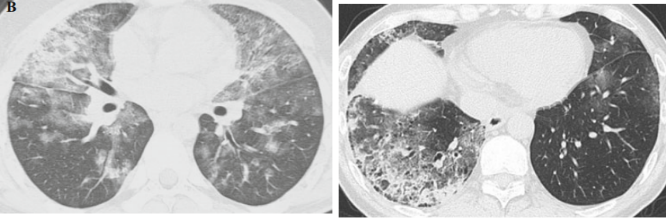

图7 24岁男性行HSCT治疗急性髓系白血病后出现呼吸困难